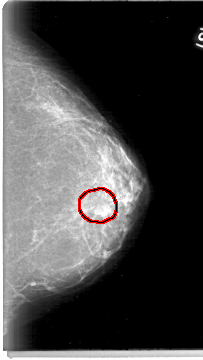

D_4004_1.LEFT_CC

LEFT_CC LINES 5386 PIXELS_PER_LINE 3031 BITS_PER_PIXEL 12 RESOLUTION 43.5 OVERLAY

FILE: D_4004_1.LEFT_CC.OVERLAY

TOTAL_ABNORMALITIES 1

ABNORMALITY 1

LESION_TYPE MASS SHAPE OVAL MARGINS OBSCURED

ASSESSMENT 0

SUBTLETY 3

PATHOLOGY BENIGN

TOTAL_OUTLINES 1

BOUNDARY